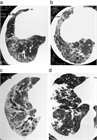

1. 特発性肺線維症(IPF)患者では「急性増悪」と呼ばれる急激な病状悪化を伴うことがある。発症すると致命率が高く、入院し早急に治療を開始する必要がある。IPF以外の間質性肺炎患者においても同様の現象が起きることがあり、安定している患者においても、急な変化があり得ることを認識し、日常から注意を払う必要がある(推奨度1)